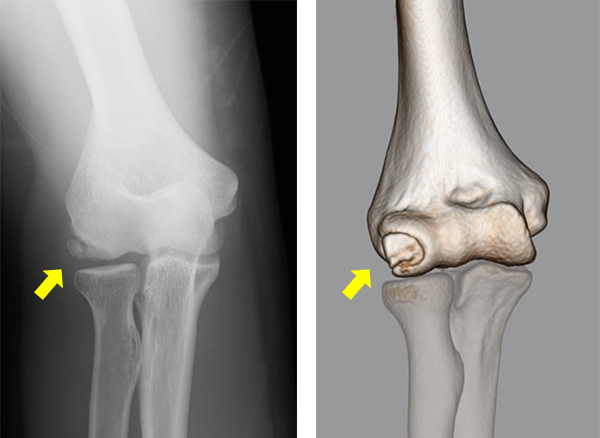

上腕骨小頭離断性骨軟骨炎のX線、CT

野球肘の診断は問診や身体所見がとても大切です。特に、疼痛部位やどの動作で痛みが出現するかが診断・治療に重要になります。当院では、問診や身体所見に加えてまず手関節X線撮影を行い関節変形の評価を行います。X線では離断性骨軟骨炎や骨棘(こつきょく)、遊離体などが認められる場合があります。また、超音波画像やCT、MRIにより靭帯損傷や炎症など含めて、病変部をより詳細に評価します。